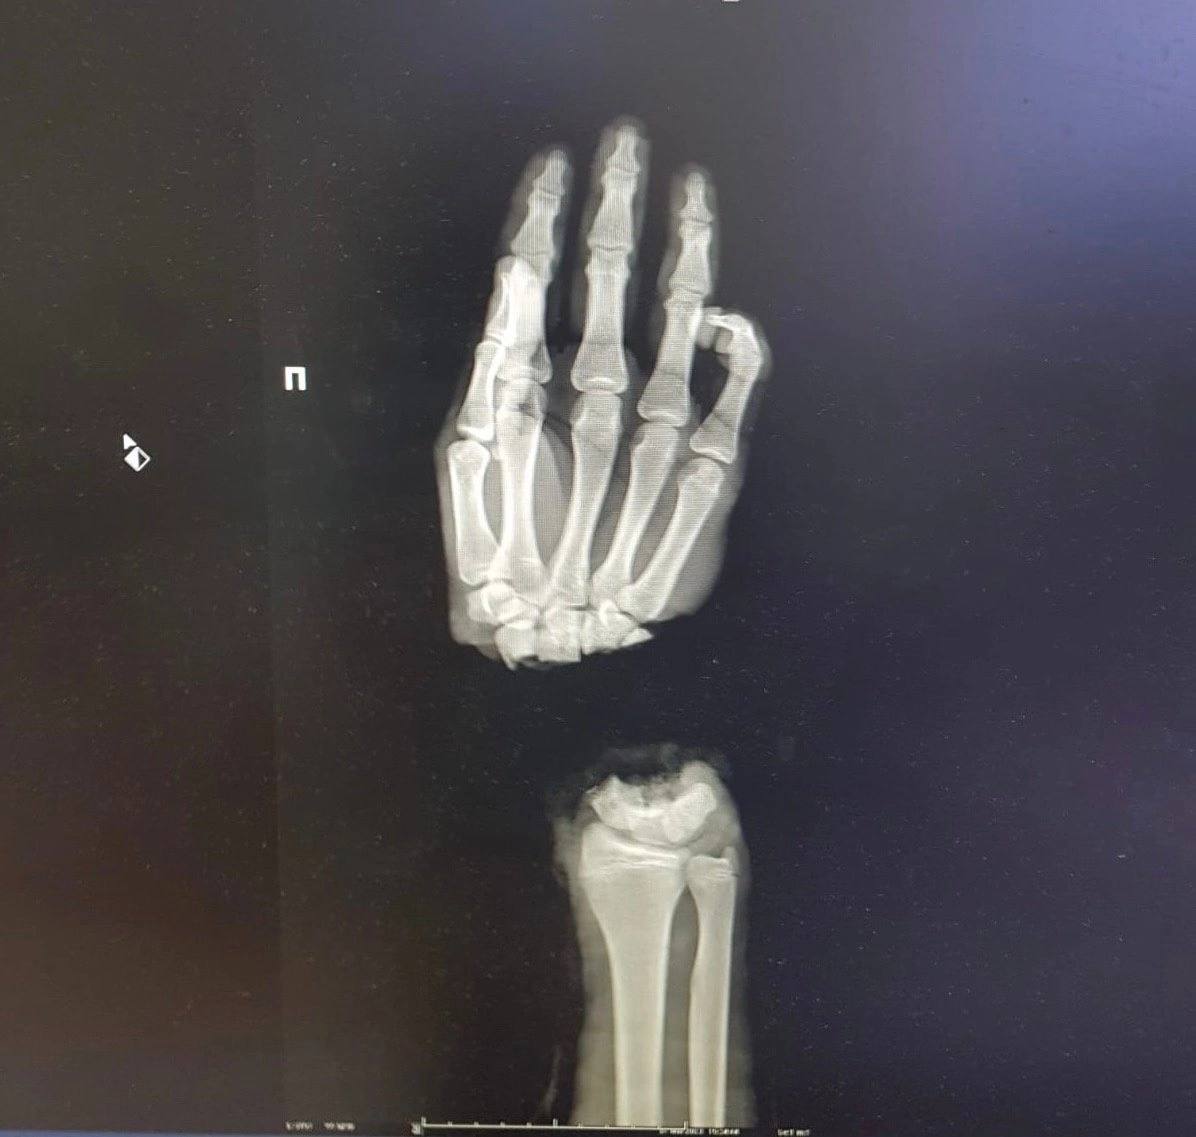

Нижегородские врачи пришили руку подростку

Нижегородские врачи помогли подростку, который отрубил себе кисть руки при колке дров.

Медики провели 16-летнему пациенту операцию по реимплантации конечности. Сейчас его состояние стабильно, кровоснабжение кисти восстановлено. Парню понадобится еще несколько операций, чтобы восстановить функциональность кисти.